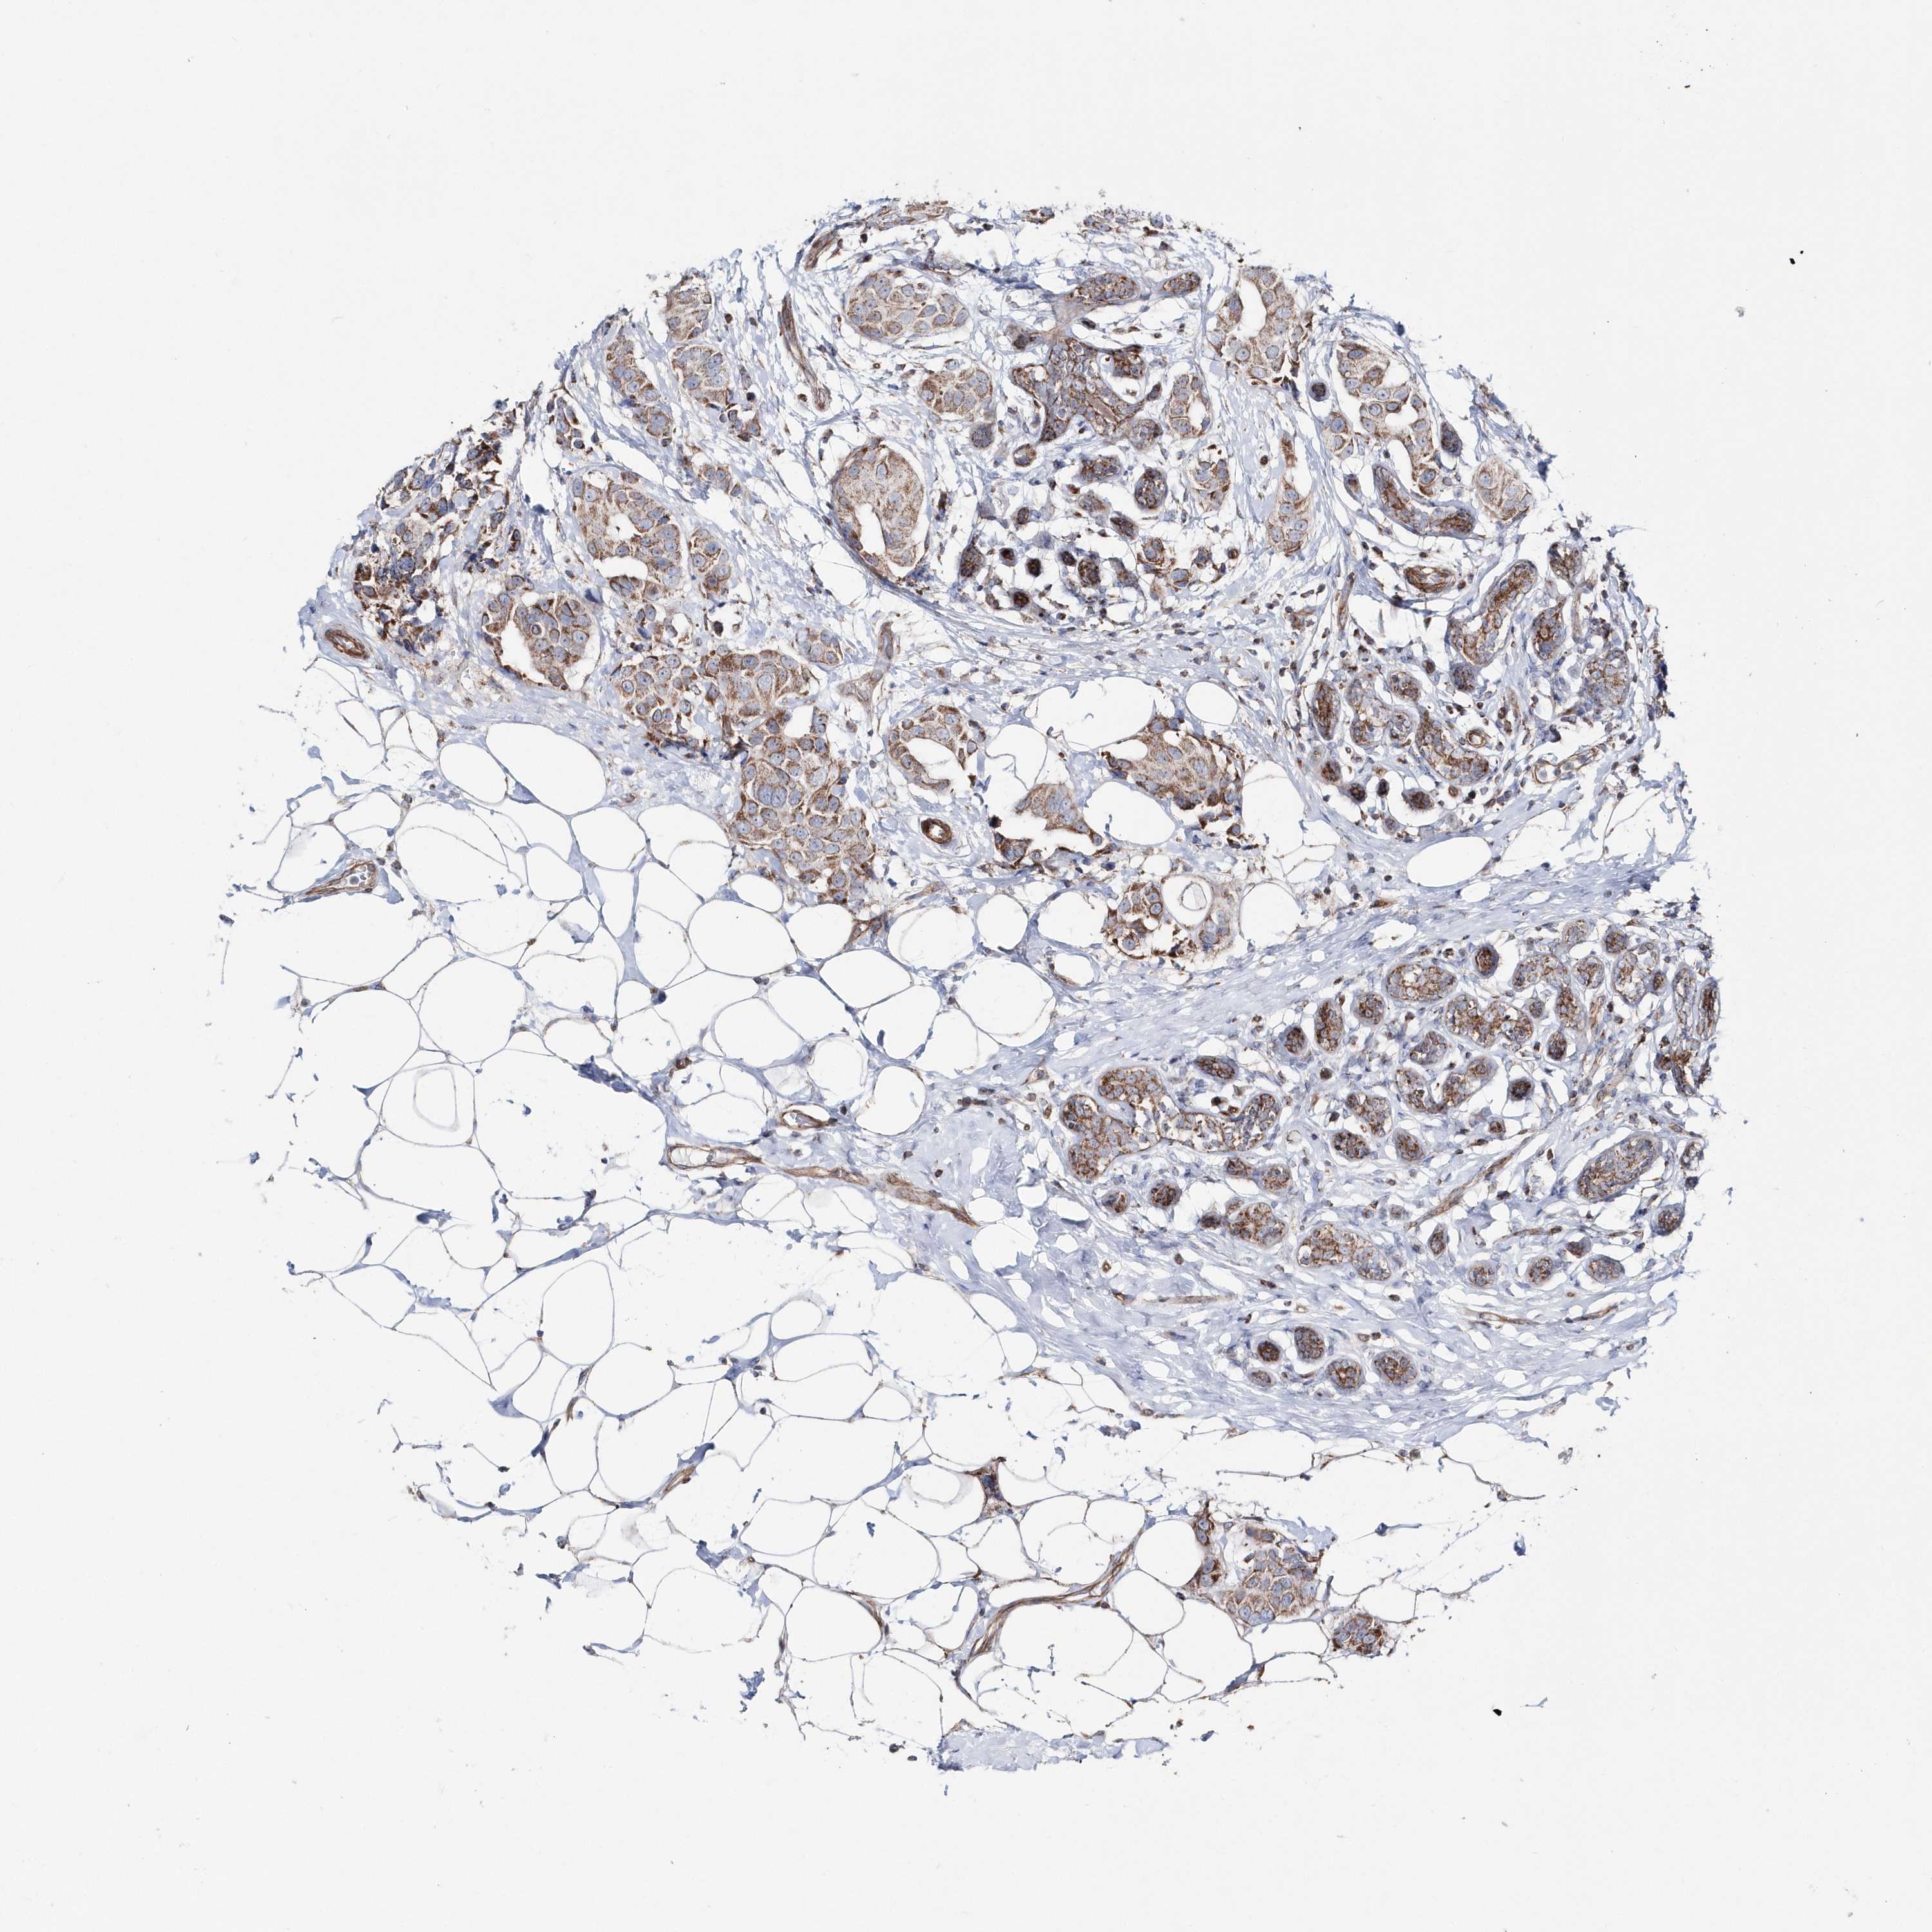

CANCER BREAST CANCER Show tissue menu

BRCA TCGA BRCA VALIDATION PROTEIN EXPRESSION

ANTIBODIES

AND

VALIDATION